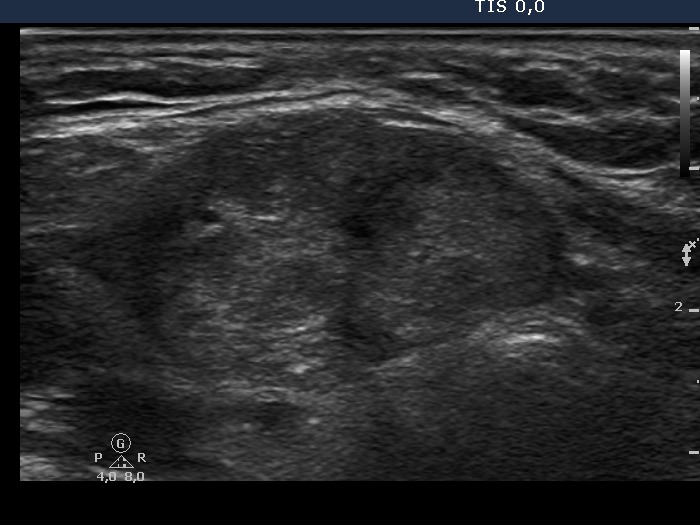

The echogenicity of the nodule - case conp 022 (ultrasonographic picture 3)

Isthmus, transverse view. There is a large mass presenting microcalcifications. The borders are partly blurred.